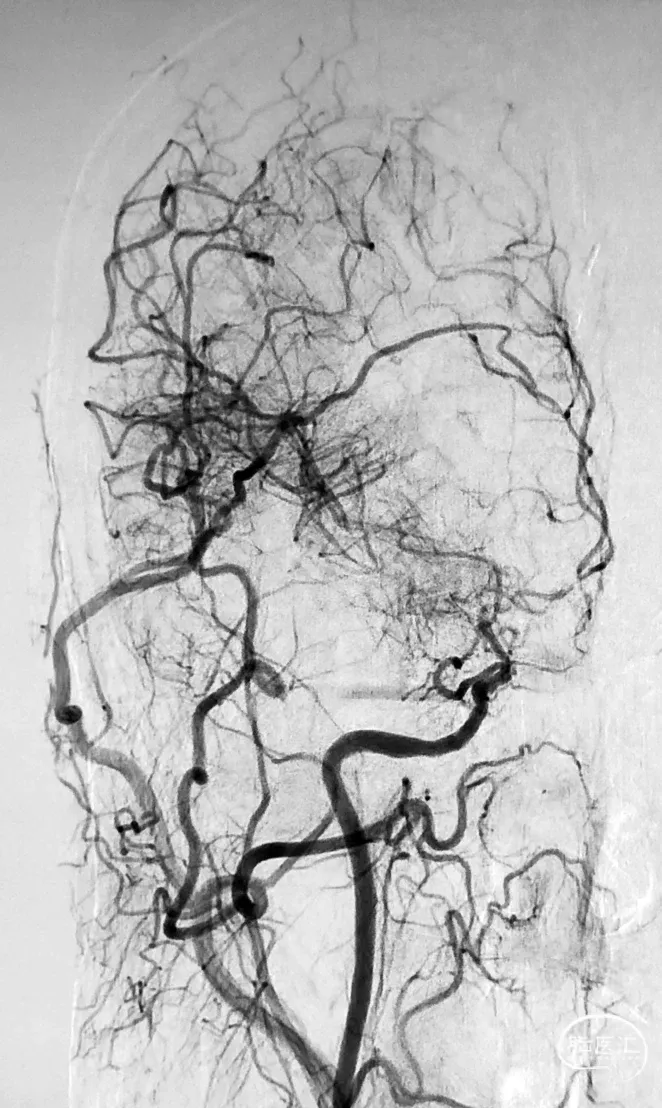

图1 从大脑后动脉(PCA)到大脑前动脉(ACA)的软脑膜侧支;A,椎动脉注射侧位图显示ACA和PCA区域之间的逆行血流(PCA→ACA顶枕支)延伸到皮质边界区;B,经后胼胝体周动脉经中央沟的血供。【7】

2021年,佟志勇等【17】回顾了2019-2020年5例STA-MCA/ACA序贯双吻合术(SDA)治疗MMD的病例,其中3例为STA-MCA-STA-ACA序贯双吻合术(世界首例)。STA中段和M4侧侧吻合,STA末端的额上回A5端侧吻合。使用单定点连续缝合法。术中测量STA压强为74mmHg(1 mmHg=0.133 kPa),A5压强为28mmHg,M4压强为29mmHg,STA侧壁压强为65mmHg。术中STA的切割流量(CF)为15~36ml/min,平均(23.6±7.7ml/min;术后1周STA流量为40~125 ml/min,平均(96.8±31.2)ml/min。术后1周STA血流量为术中CF的4.1倍。

2021年,余冠东和佟志勇等【18】回顾对照研究了STA⁃ACA和STA⁃MCA双吻合术(DBA)与STA⁃MCA双吻合术治疗MMD的疗效。纳入2017-2020年的32例ACA供血区缺血的MMD患者共计41例次手术,分别行STA⁃ACA和STA⁃MCA 双吻合术联合EMS(ACA 组,10例计10例次手术)(2019-2020年)和STA⁃MCA双吻合术联合EMS(MCA 组,25例计31例次手术)。结果显示:ACA组治疗ACA供血区缺血的MMD,桥血管通畅性良好,可获得满意的长期疗效;与MCA组相比,ACA组STA的切割流量指数(CFI)值更高,而两组术后长期疗效相当。

图4 术后2个月头部影像学检查所见:上图,CTA显示,右颞浅动脉与大脑前动脉、右颞浅动脉与大脑中动脉吻合口通畅;

中图1,中图2,右颈外动脉正位和侧位DSA显示,右颞浅动脉与大脑前动脉、右颞浅动脉与大脑中动脉吻合口通畅;

下图,右颈总动脉正位DSA显示,右大脑中动脉M1段烟雾样血管减少。【18】